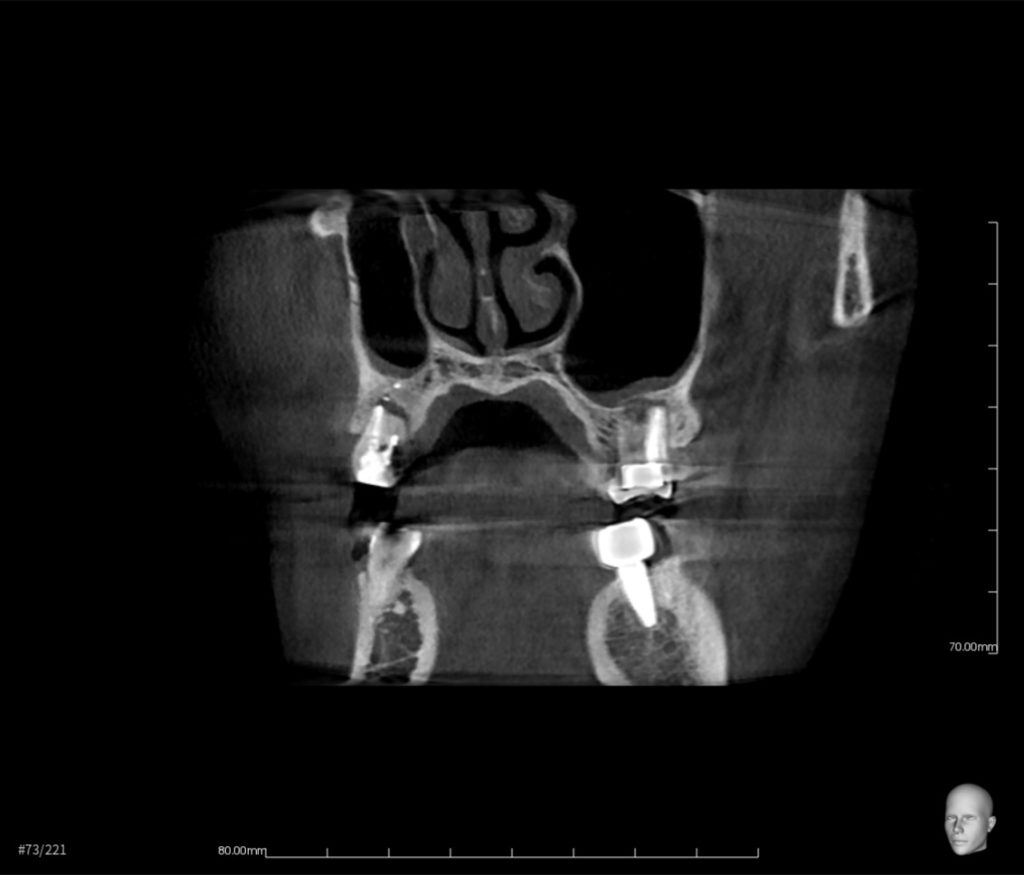

抜歯と同時にインプラントを埋入し、3ヶ月後に被せ物をセットできると思います。

抜歯即時インプラント治療の費用 約58万円(税抜)